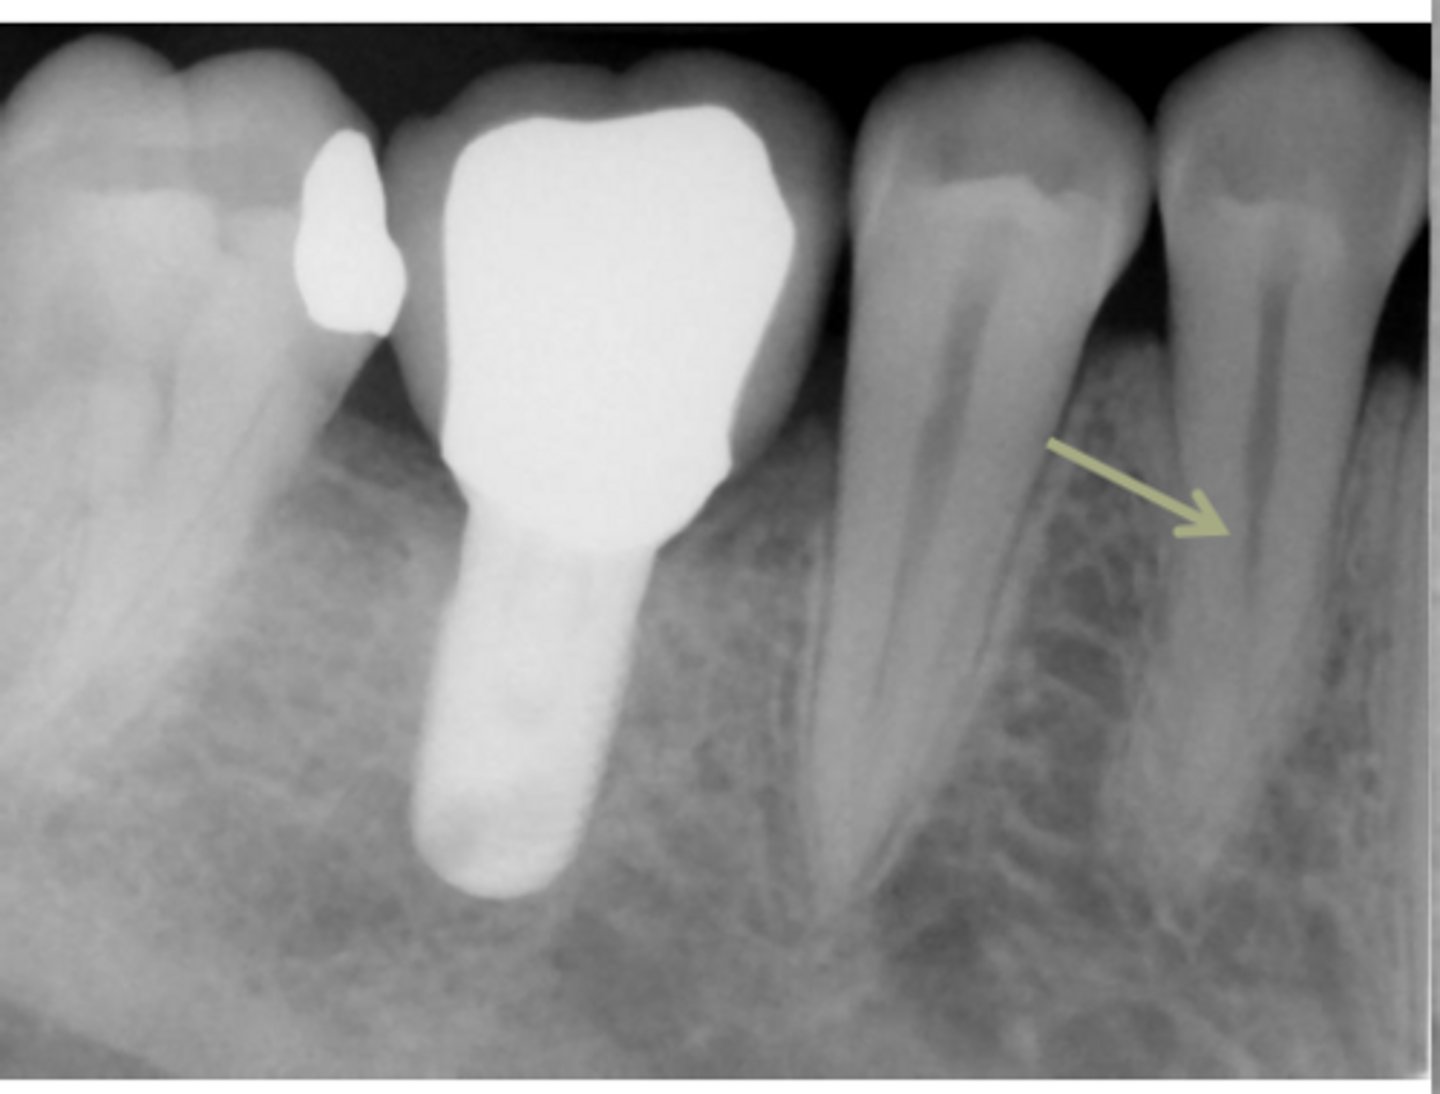

ID the problem:

- Ballooning out of root canal

internal resorption

How can you confirm if a root has internal resorption?

Take a few different angles